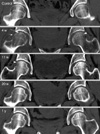

Fig. 2

MR images taken at 2 weeks postpartum demonstrate the presence of a typical bone marrow edema pattern in both proximal femurs. T1-weighted coronal image (upper) shows decreased signal intensity area in the femoral head, neck, and intertrochanteric areas. With gadolinium enhancement (lower), the decreased intensity area was markedly enhanced.